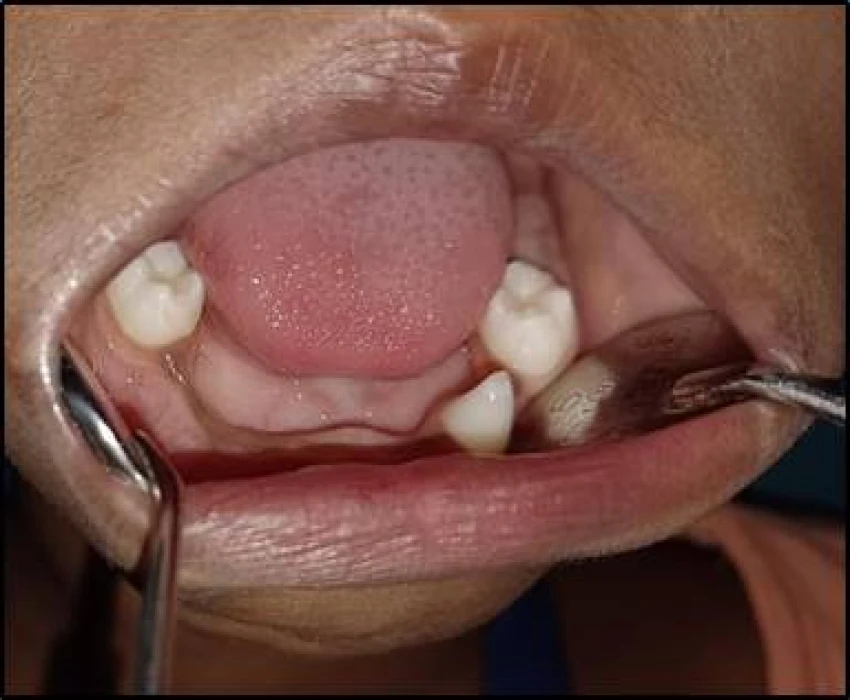

A 5 years old male patient reported to the Department of Oral Medicine and Radiology with a chief complaint of delayed eruption of teeth in lower front region of jaw since 2 years. Diagnosis of Hypohidrotic ectodermal dysplasia was given.

Hypohidrotic ectodermal dysplasia (HED) is characterized by hypotrichosis (sparseness of scalp and body hair), hypohidrosis (reduced ability to sweat), and hypodontia (congenital absence of teeth).The cardinal features of classic HED become obvious during childhood.Physical growth and psychomotor development are otherwise within normal limits.

Diagnosis is based on the episodes of hyperpyrexia, lack or type of the hair, absence of teeth and tooth buds and tooth morphology. Molecular testing approaches can include serial single-gene testing and a multigene panel.